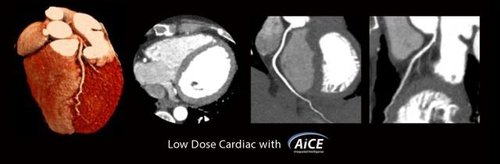

Neben der Qualität der Aufnahmen steht beim Aquilion One PRISM Edition auch die Effizienz im Fokus. So reicht eine einzige Rotation aus, um ein komplettes Herz darzustellen. Dabei wird sowohl die Dosisbelastung reduziert, als auch eine außerordentliche Gleichmäßigkeit der z-Achse garantiert. Die schnelle Bildgebung kommt besonders in der Behandlung von Schlaganfallpatienten zum Tragen, wo jede Sekunde zählt, um Hirngewebe zu retten.